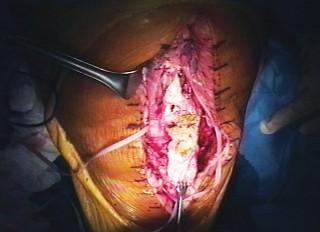

Proximal Tensioning and Fixation

The most critical step of the procedure is the proximal tensioning of the graft. The knee must be placed in full, rigid extension. The allograft quadriceps tendon is draped over the host quadriceps tendon.

The reconstruction must be tensioned maximally. A common technical error is under-tensioning the graft, which inevitably leads to a profound postoperative extensor lag. Heavy, non-absorbable sutures (such as #5 or #2 ultra-high-molecular-weight polyethylene) are used to weave the allograft and host quadriceps tendons together using a Krackow or similar locking stitch technique. The graft should be tensioned such that the reconstructed patella sits at the appropriate joint line level, avoiding patella baja or alta.

If a synthetic mesh is utilized instead of an allograft, the mesh is secured to the proximal tibia using cementation into a prepared trough or via heavy suture anchors. The mesh is then passed through the host patellar tendon remnants, over the patella, and woven into the host quadriceps tendon under maximal tension with the knee in full extension.

Given the compromised nature of the vascular supply and the added bulk of the allograft, wound healing complications are frequent. Skin necrosis over the anterior aspect of the knee can rapidly lead to deep periprosthetic joint infection or graft exposure.

Aggressive management is required for any wound breakdown. This includes prompt surgical debridement and, frequently, the mobilization of a medial or lateral gastrocnemius rotational flap to provide robust, vascularized soft tissue coverage over the reconstruction.